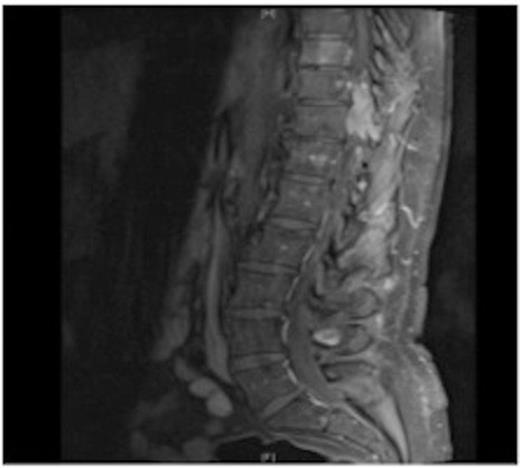

MRI showing the extra-dural tumour and extension into the soft tissue of the back

A one-year history of lower back pain, which was initially thought to be due to his liver metastasis, was investigated further with a full spine MRI scan. The scan revealed a large T10-11 extra-dural tumour with erosion of the T12 pedicle and extension into the soft tissue of the back. As a result of this discovery, the patient was referred for radiotherapy. Prior to commencement of this the oncologist requested a neurosurgical opinion from us.